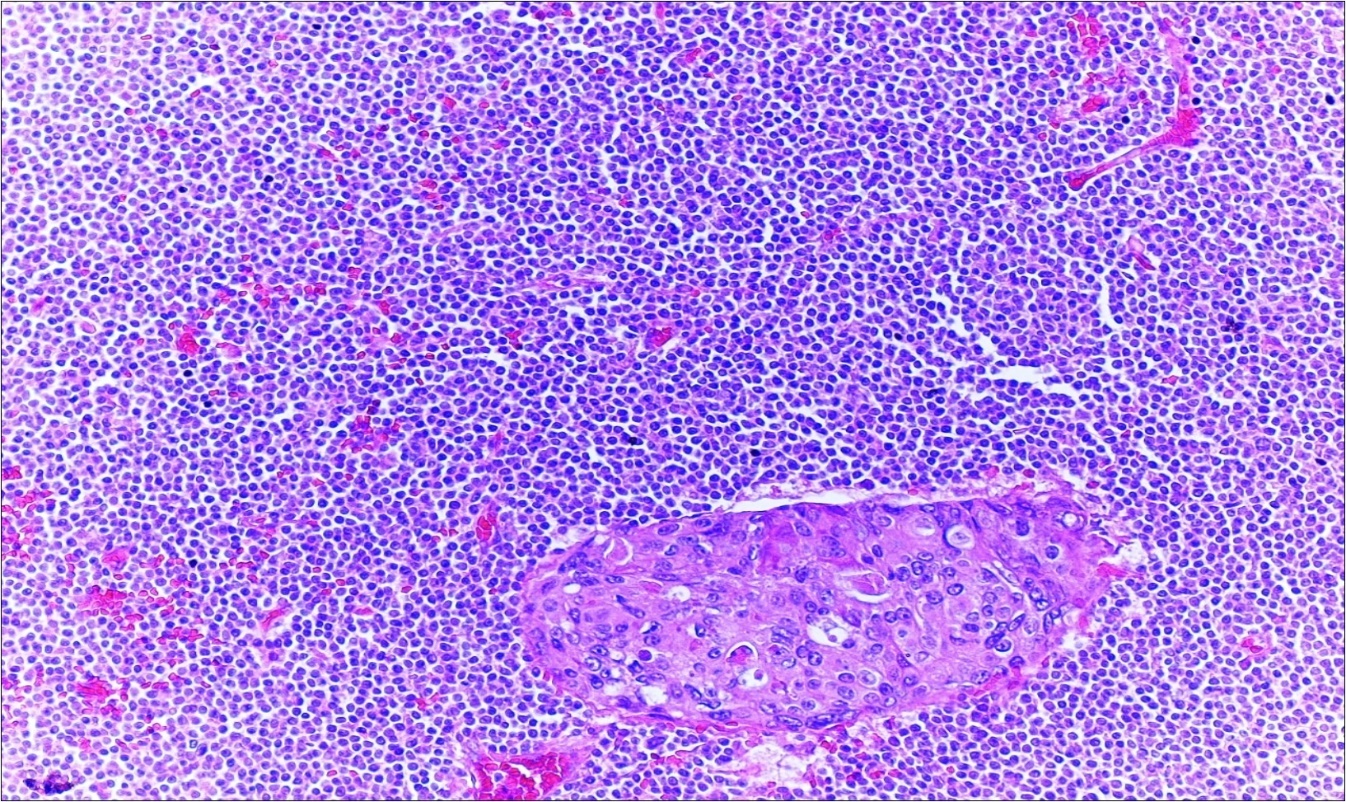

A 63-year-old woman presented to the Department of General Surgery as an outpatient with abdominal pain. Physical examination showed the signs of acute appendicitis and appendectomy was performed. During microscopic examination, a small focus of atypical monotonous lymphoid cell population was seen and the material was sampled totally. The pathological examination revealed MALT lymphoma (Figure 1), with diffuse positivity of cluster of differentiation (CD) 20 (Figure 2), CD 79a and B-cell lymphoma (Bcl- 2) (Figure 3) with just a few CD3 positive lymphoid cells. However, no evidence of adenocarcinoma was found in the appendectomy specimen. After the diagnosis of lymphoma, a complete colonoscopy was planned and this revealed a solid tumoral mass in the caecum measuring 5x4x4 cm. Computed tomography of the abdomen and pelvis revealed mesenteric lymphadenopathy associated with a mass in the caecum with multiple nodules in liver consistent with metastasis (Figure 4). Frozen sections were not obtained since the treatment method would not be affected. The patient underwent anterior resection with regional lymphadenectomy, with the pathological assessment of the resected specimen revealing a collision tumor consisting of a poorly differentiated adenocarcinoma extending through the muscularis propria with MALT lymphoma (Figure 5). Microscopic evaluation of the 11 regional lymph nodes in the mesentery of the resected colon and liver biopsy showed diffuse infiltration of MALT lymphoma with metastasis of adenocarcinoma (Figure 6). According to immunohistochemistry, atypical lymphocytes were positive for CD 20, Bcl-2, and negative for CD3, CD5, CD10, CD23, Bcl-6, terminal deoxynucleotidyl transferase, and cyclin D1. The proliferation fraction (MIB-1 immunostaining) was approximately 20%. The morphological and immunohistochemical findings were used to confirm the diagnosis of synchronous presentation of MALT lymphoma and colon adenocarcinoma within the caecum, mesenteric lymph nodes and liver metastases.

Figure 1.Appendix lumen infiltrated with B lymphoid cells (h&e;x100)

Figure 6.Adenocarcinoma with MALT lymphoma infiltration of lymph node (h&e;200)